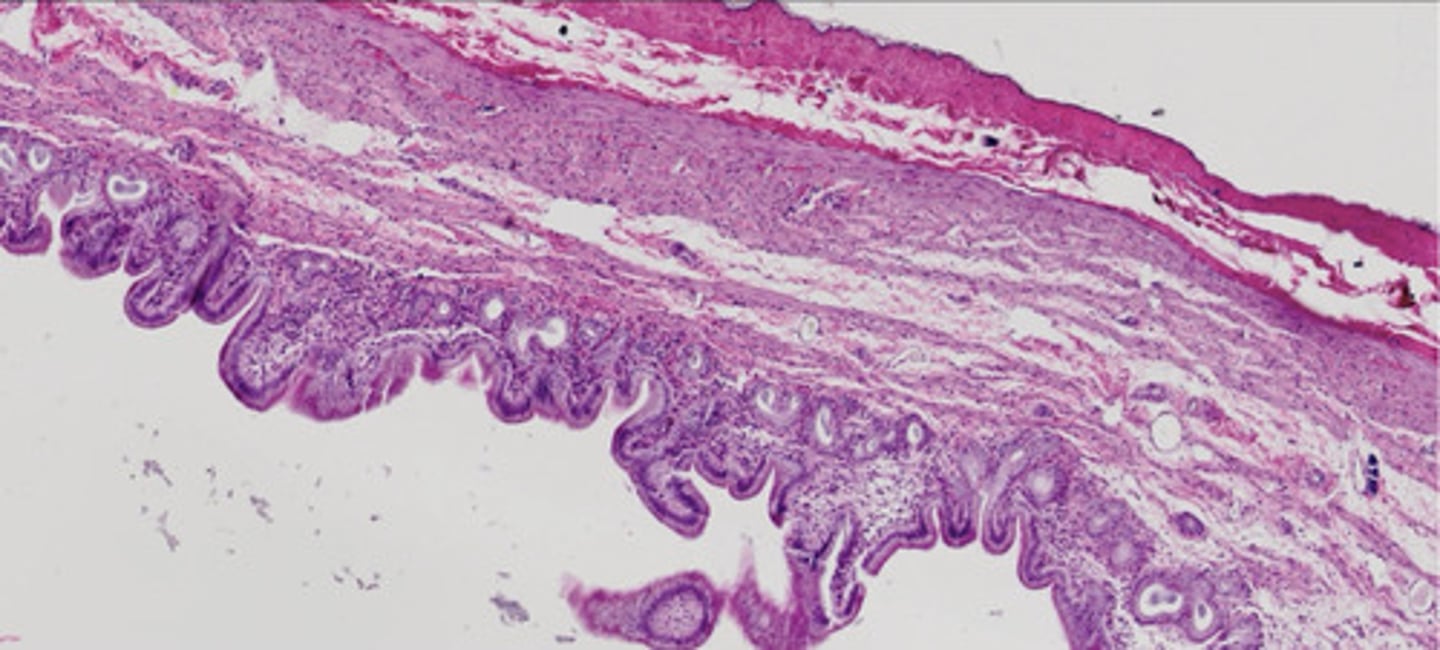

Pęcherzyk żółciowy (H+E)